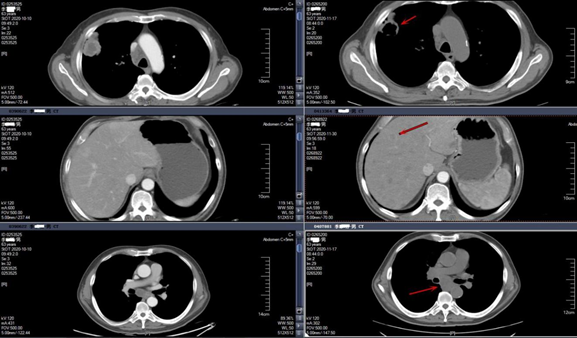

入院CT结果

一周期后CT结果对比图

2020-12-21(左)与2020-11-17(右)CT结果

2020-12-23(左)与2020-11-30(右)CT结果